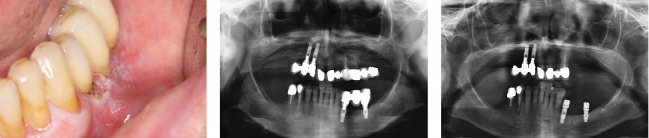

口腔扁平苔藓患者有时会发展为恶性过程,发展为口腔鳞状细胞癌或其他类型的癌症。密切监测病变和早期诊断对提高患者生存率非常重要。一旦进行了癌症治疗,除了解决美学后遗症外,恢复咀嚼和发音功能的治疗选择也很重要。在目前的临床病例中,我们展示了一位接受治疗并随访了很长一段时间的患者,她的癌症和随后的种植体康复。

Patients with oral lichen planus can sometimes develop malignancy of the process and develop oral squamous cell carcinoma or another type of cancer. Close monitoring of the lesions and early diagnosis is important to increase patient survival. Once cancer treatment has been performed, the therapeutic options for restoring masticatory and phonatory function, in addition to resolving the aesthetic sequelae, are important. In the present clinical case, we show a patient who was treated and followed over a long period of time for both her carcinoma and her subsequent rehabilitation with implants.